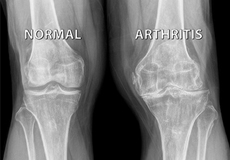

Knee Arthritis

Joint surfaces are covered by a smooth covering called cartilage. This allows pain-free, smooth movement between the bones.